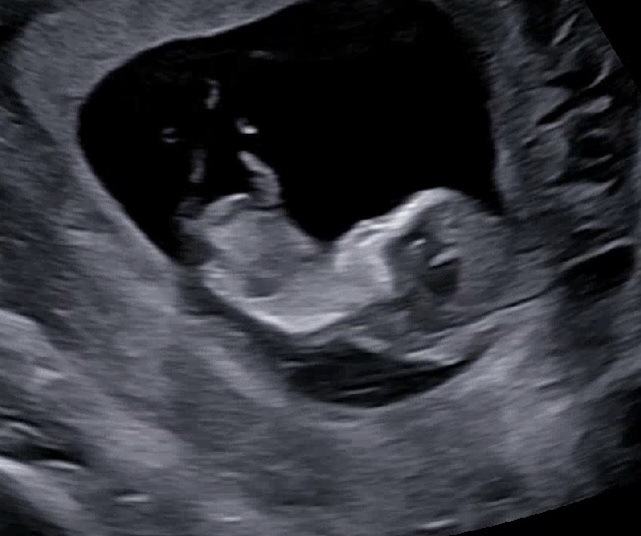

뭐가 보이는것도같고 아닌것도같아여 성별한번 봐주세용ㅎㅎ 편히 의견주세여

이 초음파상으론 알 수 없어요~~